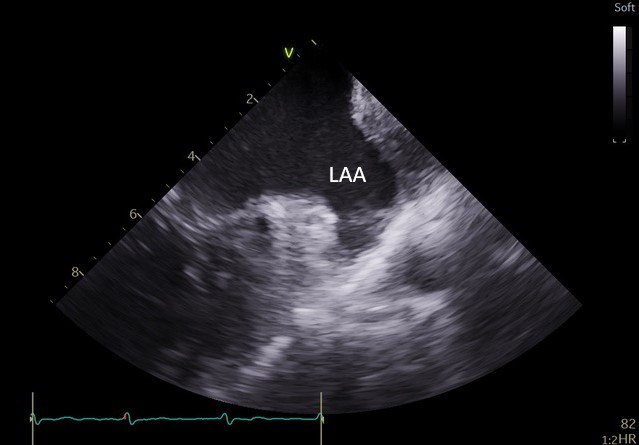

Specjaliści z Pracowni Kardiologii Inwazyjnej I Kliniki Kardiologii UCK przeprowadzili 3 zabiegi zamknięcia uszka lewego przedsionka (ang. LAAO – left atrial appendage occlusion) z wykorzystaniem systemu echokardiografii wewnątrzsercowej (ang. ICE – intracardiac echocardiography).

– U części pacjentów kwalifikowanych do LAAO ryzyko związane z wykorzystaniem obrazowania metodą TEE jest zbyt wysokie ze względu na poważne zmiany chorobowe przełyku. To dotychczas uniemożliwiało wykonanie zabiegu. Obrazowanie metodą ICE pozwala na bezpieczne wykonanie zabiegu zamknięcia uszka lewego przedsionka również w tej grupie chorych, ponieważ specjalną sondę ultrasonograficzną wprowadza się nie do przełyku, lecz przez układ żylny pacjenta, bezpośrednio do jam serca – mówi dr Dariusz Ciećwierz, koordynator Pracowni Kardiologii Inwazyjnej I Kliniki Kardiologii UCK z I Katedry i Kliniki Kardiologii GUMed. – Dodatkową korzyścią tego rozwiązania jest większy komfort pacjenta w trakcie zabiegu, dzięki czemu można uniknąć sedacji czy znieczulenia ogólnego.

W ramach przygotowania do wprowadzenia metody do praktyki klinicznej w UCK, zespół zabiegowy miał możliwość przetrenowania jej zastosowania na zaawansowanym symulatorze w Centrum Symulacji Sercowo-Naczyniowej GUMed. Zabiegi wykonano u dwóch pacjentów z zaawansowanymi żylakami przełyku z powodu marskości wątroby oraz u pacjentki z wrodzoną naczyniakowatością krwotoczną (choroba Rendu-Oslera-Webera). Nadzór merytoryczny w trakcie pierwszych przeprowadzonych zabiegów zapewnił dr hab. Witold Streb, kardiolog ze Śląskiego Centrum Chorób Serca w Zabrzu.